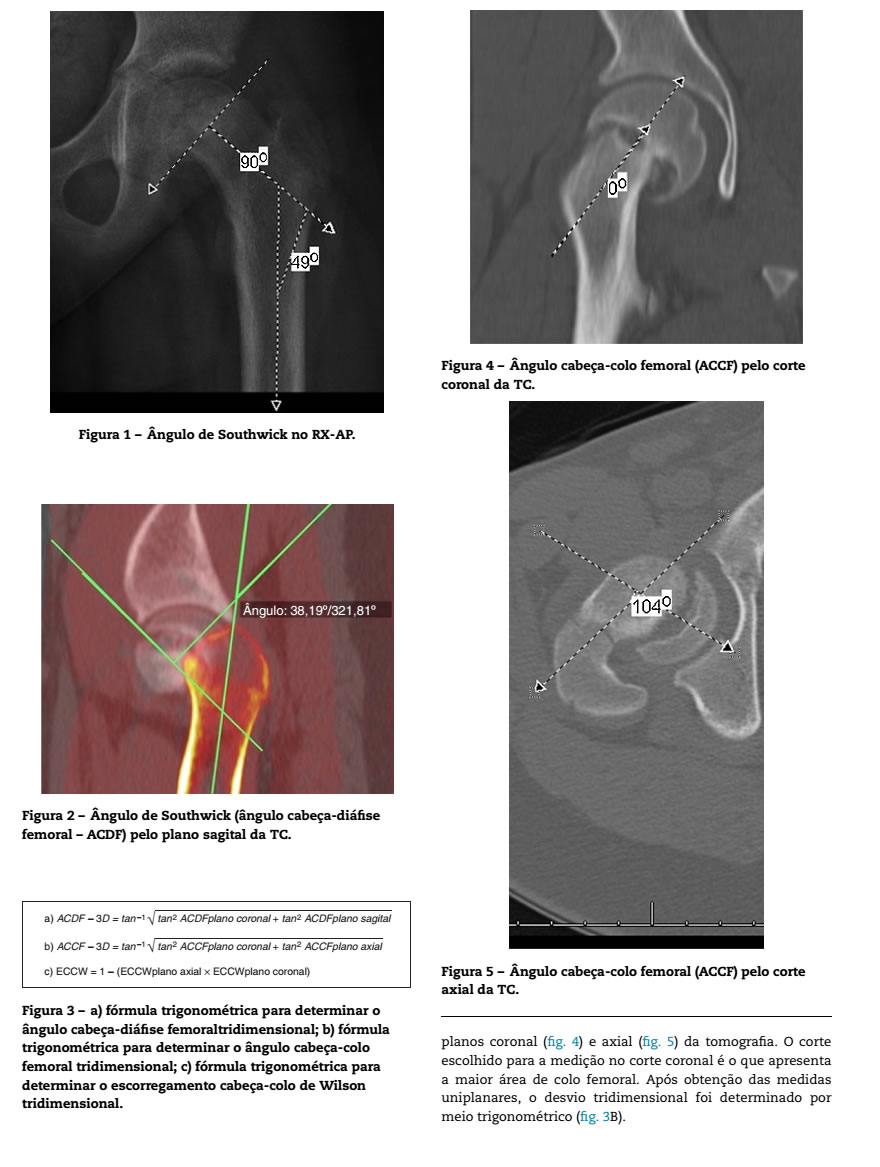

Revista Brasileira De Ortopedia Estudo Comparativo Dos Angulos Radiograficos E Tomograficos Na Epifisiolistese Do Femur Proximal

rbo.org.br